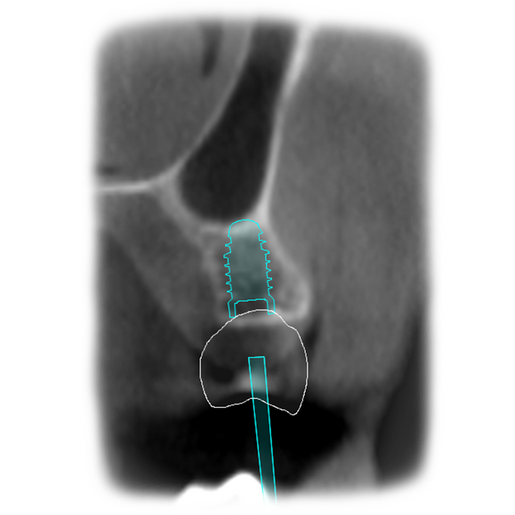

It is our most comprehensive planning option, and includes all the 3D treatment simulations needed for each case, such as ortho, perio, implants, grafts and orthognathic surgery.

Our 3D simulations showcase facilitate a deeper understanding of the required procedures. This leads to the creation of a broader treatment plan and enables a more efficient communication with your patients.